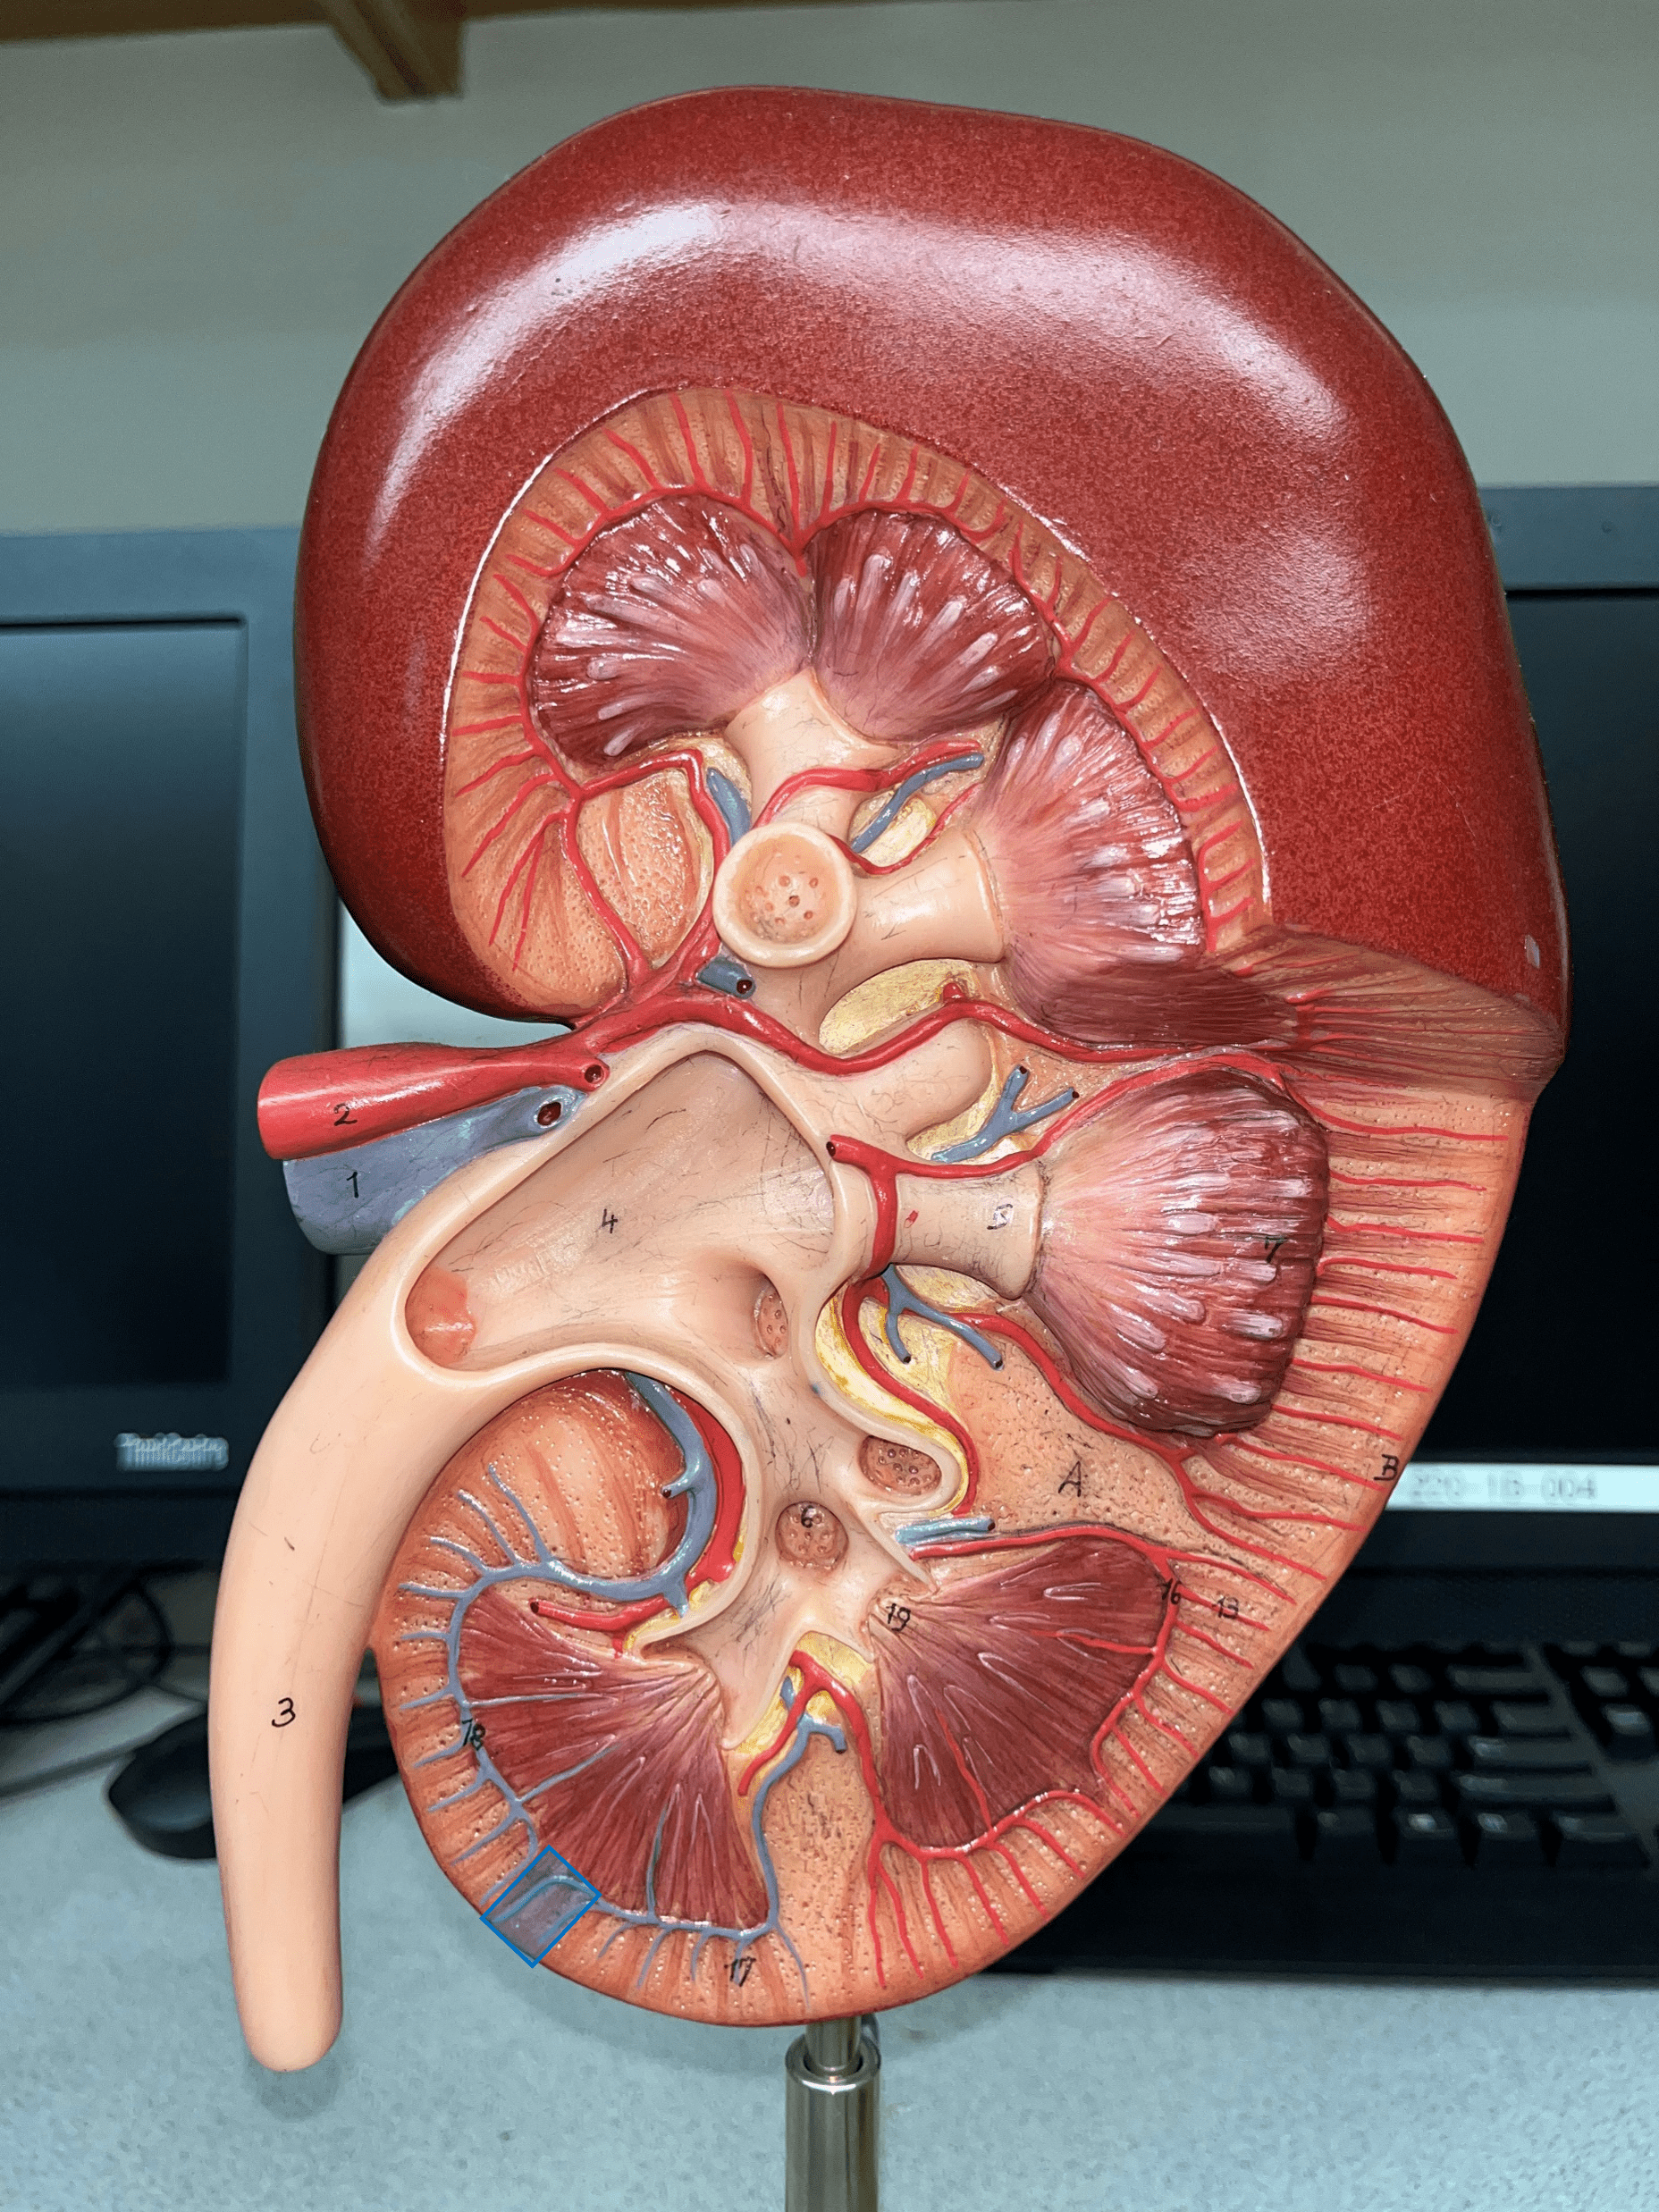

interlobular vein

arcuate vein

interlobar vein

renal vein

interlobar artery

arcuate artery

interlobular artery